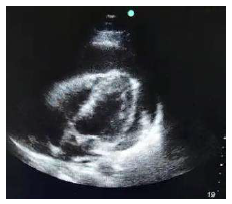

Um paciente de 28 anos de idade foi encaminhado para a sala de emergência com relato de desconforto respiratório. Na admissão, verificou-se pressão arterial de 70 mmHg × 40 mmHg, frequência cardíaca de 130 bpm, frequência respiratória de 20 ipm e saturação de O2 igual a 95% em ar ambiente. Foi realizada uma ultrassonografia à beira do leito.

Abaixo está representada a imagem do corte quatro câmaras.

A partir do caso clínico acima, assinale a alternativa que apresenta o quadro clínico mais provável do paciente.